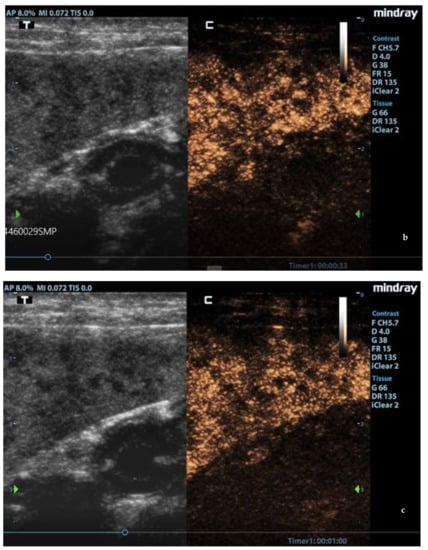

Enhancement in the moth-eaten parenchymas had a heterogeneous distribution pattern with hypoenhancement/no enhancement areas in both the wash-in and wash-out phases; in marbled spleens, enhancement intensity was weak and heterogeneous (Figure 4 and Figure 5).

Figure 4.

Moth-eaten spleen images acquired during CEUS exam. The heterogeneous enhancement of the parenchyma was persistently observed at: (a) 13 s, (b) 33 s, and (c) 60 s after contrast injection. F: probe’s frequencies; D: distance; G: gain; FR: frame rate; DR: dynamic range; AP: acoustic power; MI: mechanichal index; TIS: tissue imaging specific; M9: ultrasound system; T: tissue; C: contrast. Green arrows: focal points.

Figure 5.

CEUS images at the end of the wash-in phase in (a) moth-eaten, (b) marbled (heterogeneous enhancement), and (c) normal (homogeneous enhancement) spleens. F: probe’s frequencies; D: distance; G: gain; FR: frame rate; DR: dynamic range; AP: acoustic power; MI: mechanichal index; TIS: tissue imaging specific; M9: ultrasound system; T: tissue; C: contrast. Green arrows: focal points.